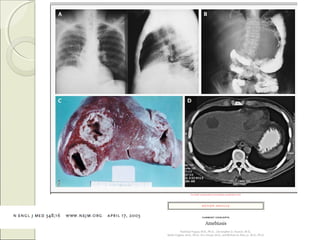

3-3- ABSCESO HIDATÍDICOABSCESO HIDATÍDICO

* Echinococcus granulosum.

Perros: hospederos definitivos.

-----------

Desarrollo de quístes hidatídicos:

- 2/3 hígado.

- 1/3 pulmones.

Lab: Eosinofilia (40%)

3.1 Clínica:3.1 Clínica:

- Hepatomegalia.

- Dolor a palpación en HD.

- Complicaciones:

- Ruptura hacia peritoneo.

- Urticaria, choque anafiláctico.

- Fístula biliar: colangitis.

-------

Rx tórax: Quístes pulmonares (10%)

* TAC:* TAC: Infección presente -

pasada

3-3- ABSCESO HIDATÍDICOABSCESOHIDATÍDICO * Echinococcus granulosum. Perros: hospederos definitivos. ----------- Desarrollo de quístes hidatídicos: - 2/3 hígado. - 1/3 pulmones. Lab: Eosinofilia (40%)

3.1 Clínica:3.1 Clínica: -Hepatomegalia. - Dolor a palpación en HD. - Complicaciones: - Ruptura hacia peritoneo. - Urticaria, choque anafiláctico. - Fístula biliar: colangitis. ------- Rx tórax: Quístes pulmonares (10%)

* TAC:* TAC:Infección presente - pasada